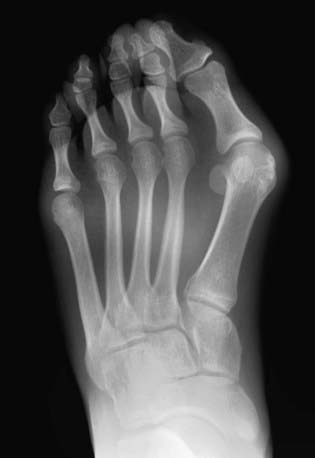

Radiographic Evaluation

Weight-bearing AP and lateral radiographs of the feet are obtained. On the AP view, common measurements include the angular relationships between the 1st and 2nd metatarsals (intermetatarsal angle, <10 degrees is normal) and between the 1st metatarsal and the proximal phalanx (hallux valgus angle, <25 degrees is normal) (Fig. 666-8). The orientation of the 1st metatarsal-medial cuneiform joint is also documented. On the lateral radiograph, the angular relationship between the talus and the 1st metatarsal helps to identify a midfoot break associated with pes planus. Radiographs are more helpful in surgical planning than in establishing the diagnosis.

image

Figure 666-8 Hallux valgus in a 14 yr old girl.

(From Slovis TL, editor: Caffey’s pediatric diagnostic imaging, ed 11, vol 2, Philadelphia, 2008, Mosby.)